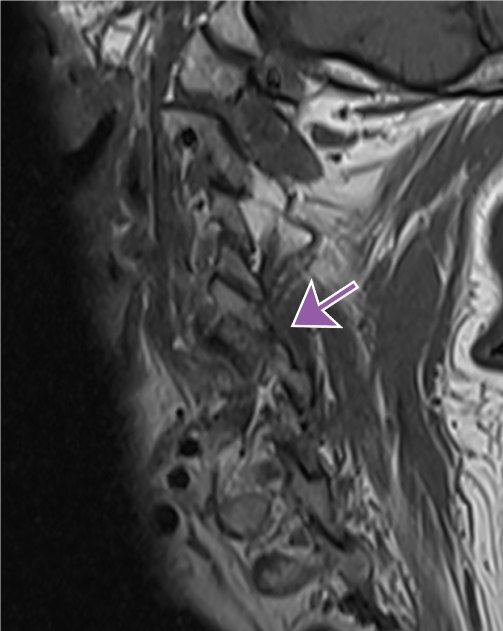

Perched Facets

Malalignment of the facet joints with the inferior articular process of C5 sitting anteriorly “perched” on the superior articular process of C6.

Widening of the interspinous distance.

Search Pattern alert: Examine facet joints on parasagittal images.